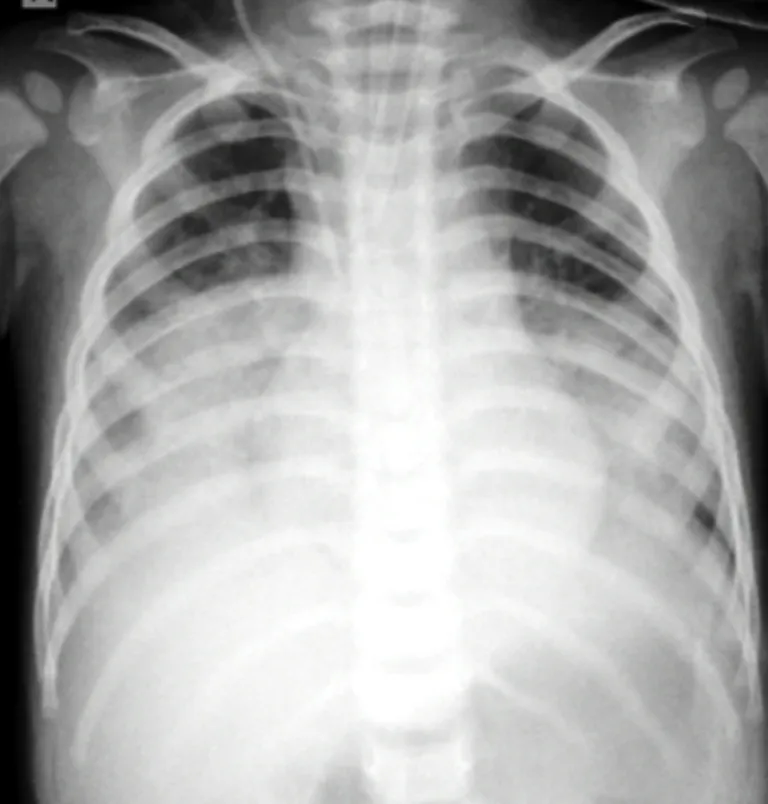

Bé NTH bị viêm phổi nặng sau khi uống nhầm dầu thắp đèn.

Trước đó, ngày 29-12, bé H được chuyển đến BV Sản nhi Nghệ An cấp cứu trong tình trạng tím tái, khó thở, nguy kịch. Ngay lập tức các y và bác sĩ của BV đã nhanh chóng hỗ trợ hô hấp bằng máy áp lực cao cho trẻ, dùng kháng sinh phổ rộng…

Bác sĩ Nguyễn Hùng Mạnh, Trưởng khoa Hồi sức tích cực chống độc, BV Sản Nhi Nghệ An cho biết, ngộ độc do uống nhầm hóa chất rất dễ xảy ra ở trẻ em. Các trường hợp uống xăng, dầu hỏa có thể gây viêm phổi bởi bệnh nhân dễ dàng hít phải hơi độc của hóa chất.